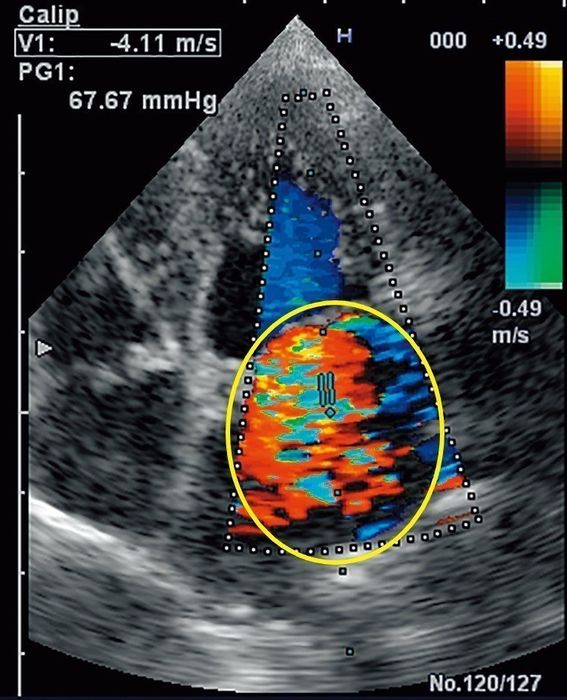

「僧帽弁閉鎖不全症」の犬の心臓エコー画像。円で囲んでいるところが、逆流した血液を示しています

症状が表に出ない初期のころであっても、エコー検査と聴診によって、わんちゃんの心臓の状態を確認することができます。